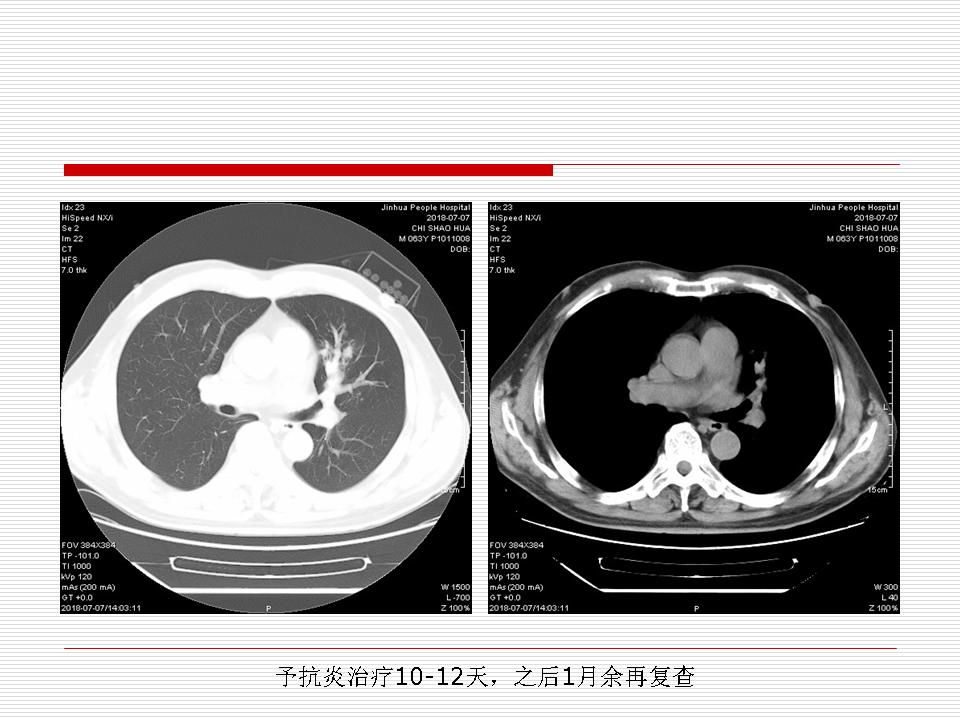

肺部阴影永恒且最重需要鉴别的是:到底是炎症还是肿瘤?但临床的病例中的影像表现难以界定或有些肿瘤特征,同时又有些炎症特点是非常常见的情况。作为临床医生我们怎么去总结分析,并找到之所以是炎症或之所以是肿瘤的细微差别或特点非常重要,也非常有用。2019.12.7浙江省2019年胸心外科学学术年会在宁波召开时,我的临床病例分析与经验总结<那些像肺癌的炎症与像炎症的肺癌>获得在大会交流的机会,以下为该PPT的内容,与你分享,希望对同道有益,有借鉴与启迪。若有探讨与进一不完善的建议,欢迎文末留言讨论: